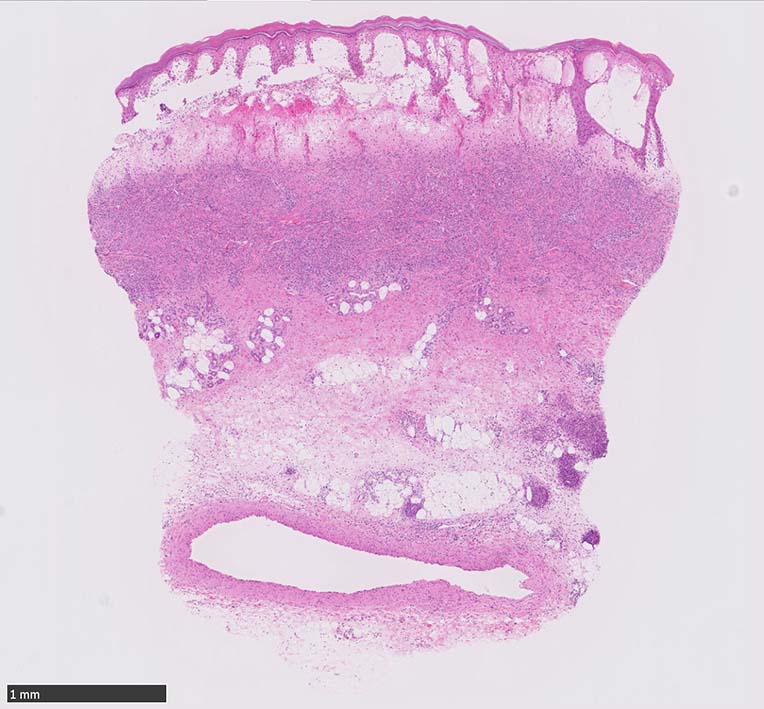

HE x40. Sweet病最盛期皮膚病変の所見があります.

表皮下水疱, 真皮上層の細血管周囲に密な好中球浸潤あり.(thumb nail clickで大きなphotoが見られます)

Case02 前胸部皮膚

73 year old male

lt

骨髄異形成症候群で入院中. 発熱, 関節痛に加えて四肢, 胸部など上半身に潰瘍形成をともなう浮腫性紅斑が出現してきた. 皮下硬結あり. Sweet症候群と診断.

中央に黒色痂皮を示す紅斑. 硬結の強い部位から生検される.

HE x40. 表皮下水疱あり. 真皮上層は浮腫状. 真皮から皮下組織にかけて, 多数の好中球が浸潤している. リンパ球, 好酸球が混在, 核破砕物を貪食するマクロファージが増加. 膠原線維にはところどころ変性が見られる.

真皮上層には核破砕物が多く, 好中球浸潤が認められる. 慢性炎症性細胞も浸潤している.

フィブリノイド壊死を呈する血管炎は認められない.

皮下脂肪織炎病変には局所的なhemophagocytosisが認められる. 血管にはfibrinoid necrosisは見られない。